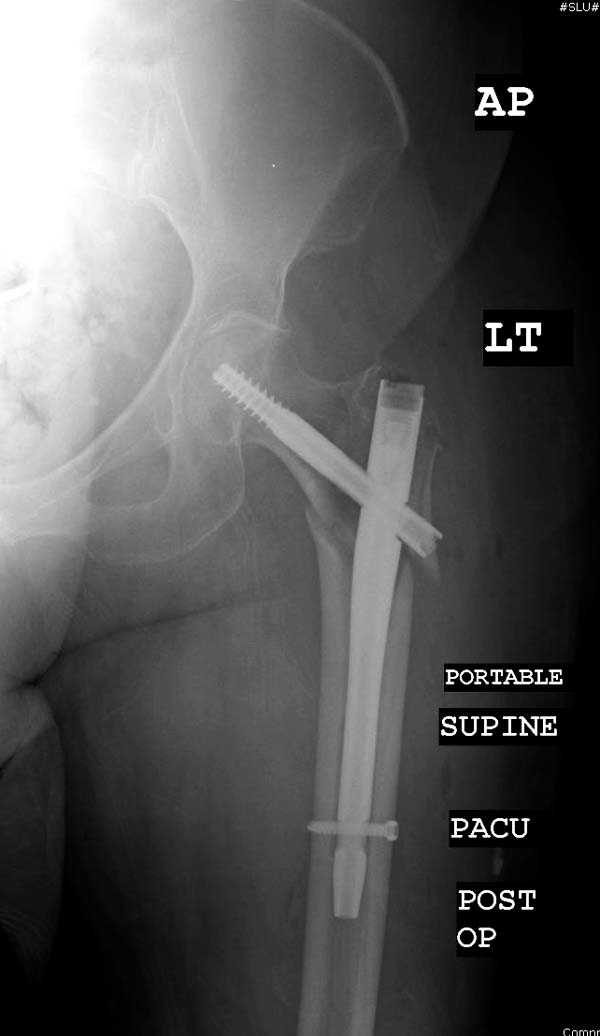

Здесь представлен случай, где в послеоперационном периоде обнаружена техническая ошибка, Gamma 3 установлен с нарушением методики. Больная в 91 лет, прооперирована через день после поступления и выписана через 48 часов.

При первом послеоперационном поликлиническом осмотре больная предъявила жалобы на боли в бедре. В серийных снимках обнаружен продольный перелом верхнего отдела бедра.

Считаем, что техническая ошибка произошла во время установки гвоздя, когда рассверливанию канала не уделили должного внимания. Канал остался узковат, и гвоздь был забит с силой. Полная нагрузка конечности приостановлена на две недели, и боли в конечности изчезли. Больная начала нагрузку и перелом срастается.-- Djoldas Kuldjanov, M.D.Associate ProfessorDepartment of Orthopedic SurgerySt. Louis University

I have a different interpretation of this case. I suspect you did not tighten the set screw all the way in order to allow sliding of the lag screw and fracture fragment compression, as you would for a standard intertrochanteric hip fracture. This is a reverse obliquity fracture, so the result is migration of the proximal segment. I doubt reaming the canal would have prevented this. Had the set screw been fully tightened, there would be no postoperative fragment motion.

Мне тоже представляется, что это не единственная проблема. Продольные трещины заживают легко и быстро. Интересно, почему увеличился варус и

появилась медиализация дистального отломка.

Мне думается, что варусное положение проксимального отломка на последующих снимках не более чем проекционный феномен. Раскол же диафиза вдоль, наверняка, связан с чрезмерно насильственным введением штифта. Вообще, при реверсивных, да и обычных вертельных переломах, многие давно отказались от короткой Гаммы в пользу long-версии. Но в любом случае надо быть на 100 уверенным в подготовке канала.